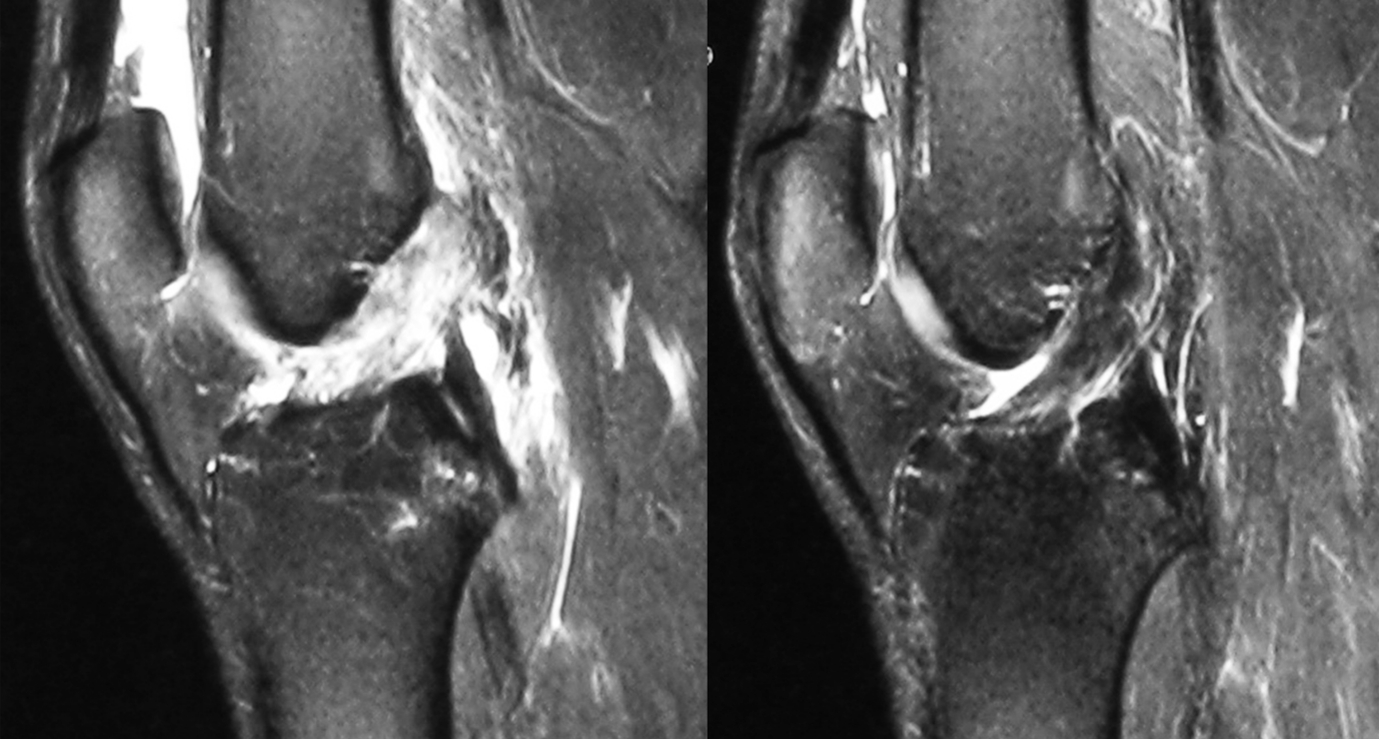

Sports medicine clinicians continue to discuss the healing capabilities of a ruptured ACL. Researchers at the Hiroshima University School of Medicine in Japan showed that an acutely injured ACL has healing capability. The researchers suggested that conservative ACL management can produce satisfactory results in individuals and continuous ACL on repeat MRI, provided the patients are willing to accept the slight risk of late ACL reconstruction and meniscal injury(8). Furthermore, the meniscus also showed healing capabilities with non-surgical treatment(7).

ACL-injured patients with repeat high-powered imaging can demonstrate intact, partially healed, or non-anatomically healed, e.g., proximal bundles attached to the PCL(9). Although healing may occur in some patients, others may have persistent tibial translation, increased risk of meniscus tears, and a non-healed ACL.

Rehabilitation protocols with or without bracing show MRI evidence of ACL healing(10,11). For example, researchers at the University of Melbourne in Australia demonstrated that 56% of the KANON participants had a healed ACL at two years and 58% at 5-years following rehabilitation alone. Furthermore, 4% had a healed ACL before undergoing delayed ACLR(11). In addition, an upcoming study from Australia shows data of very high healing rates and restored ligament stability on passive testing of fully ruptured ACLs after a novel bracing protocol.